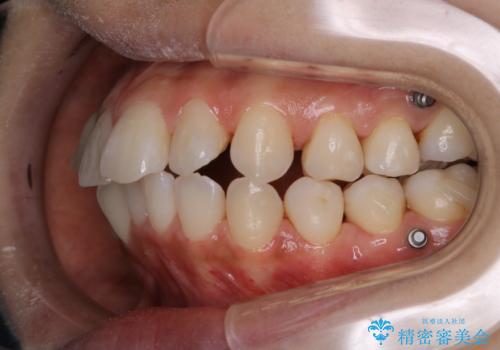

- インビザラインでのマウスピース矯正中の方です。歯についてしまったステインが気になり綺麗にしたいとのことでした。PMTC60分コースを行いました。

PMTC(保険外治療)は、毎日の歯磨きで落としきれない汚れや、コーヒ、紅茶・タバコのヤニなどの着色も除去します。目には見えない歯と歯の間・歯肉の境目・インビザライン中はアタッチメント周囲などに残っているプラーク(歯垢)もしっかり取り除きます。PMTCでは専門的な機械や材料を使用して、徹底的に汚れを除去するため、虫歯・歯周病・口臭予防などにつながります。